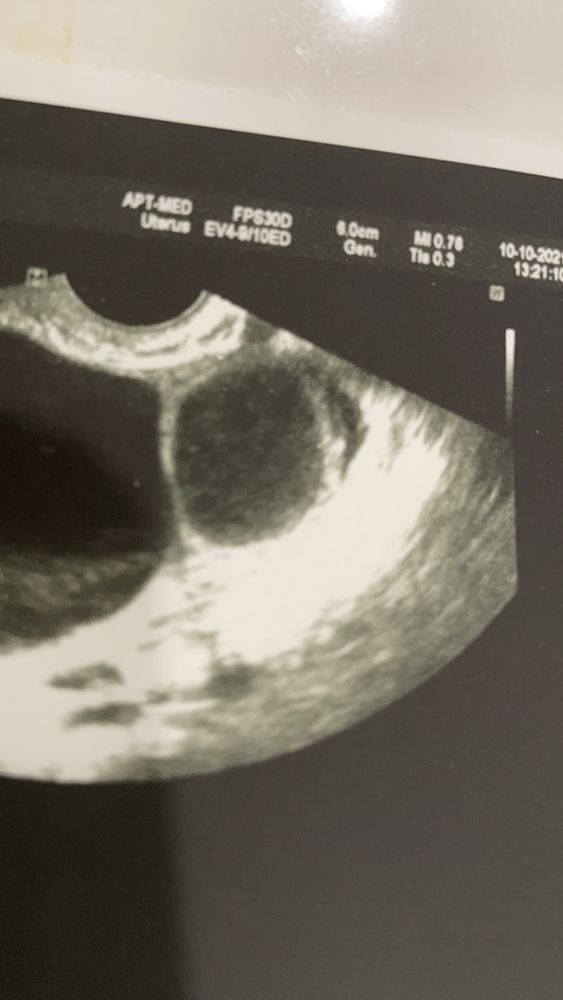

девочки, подскажите , пожалуйста. Впервые за всю жизнь у меня появилась киста таких размеров 5 см( раньше была 2 мм и то 1 раз). Всегда цикл где-то 26 дней, овуляция на 12 день, проводила тесты на 12,13,14 овуляции не было , ну и я потом забила , решила сходить на 26 день цикла проверить была ли овуляция , а нашли кисту, да ещё и не одну! Вторая узисты пока разводят руками и лишь предполагают что это ЖТ. С мужем планируем, вот мне интересно овуляция могла быть попозже из-за этого ? Стоит ли мне питать надежды на беременность, сейчас второй день задержки, но при такой кисте это нормально вроде. Тесты только клиаблю слегка полосатят, но они и так часто реагентят. На фото узи позавчера

Ирина, я буду рада любому исходу событий 😂я уже жду месячных как никогда, потому что мечтаю, чтобы они быстрее рассосались , чтобы нормально заниматься спортом!но эти узисты и врачи говорят, что даже Б исключить нельзя, и даже врач сказала, что это похоже на ЖТ…. Вблизи на фото чуть другая структура там

Ирина, подскажите, даже приближённее не похоже на ЖТ

Ксюша, как по мне - они идентичны у вас на фото и это оба фолликулы, фолликул на узи имеет чёткие границы и внутри как бы чёрное пространство. 5 лет стажа планирования и моя любимая узистка мне показывала и рассказывала как и что)) у меня качество не такое хорошее, но вот на одном фото фолликул 13 мм и жёлтое тело 17мм, жёлтое тело совсем другой консистенции